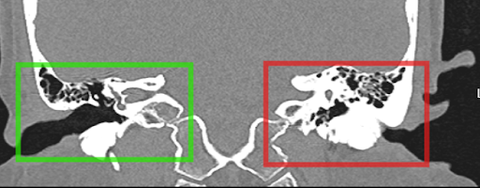

Khối đậm độ như xương với các thành của ống tai xương, lan vào ống tai ngoài, làm chít hẹp gần như toàn bộ ống tai ngoài trái của chị T. - Ảnh: BVCC

Trước khi nhập viện khoảng 1 tháng, tai chị T. xuất hiện tình trạng ù, nghe kém và có dịch đục chảy ra ngoài. Qua thăm khám tại một cơ sở y tế tư nhân, bác sĩ phát hiện ống tai ngoài bên trái của chị bị chít hẹp trên 99% bởi một khối bất thường.

Sau đó, chị T. tiếp tục đến Bệnh viện TP Thủ Đức thăm khám và được chẩn đoán xác định bị lồi xương ống tai ngoài. Tình trạng này không chỉ ảnh hưởng đến thính lực mà còn gây nguy cơ viêm nhiễm tái diễn do ứ đọng dịch, ráy tai.

Vì kích thước lồi xương quá lớn, ê kíp phẫu thuật tại bệnh viện đã mổ qua đường sau tai thay vì can thiệp nội soi thông thường. Ca phẫu thuật tiến hành vào cuối tháng 8-2024.